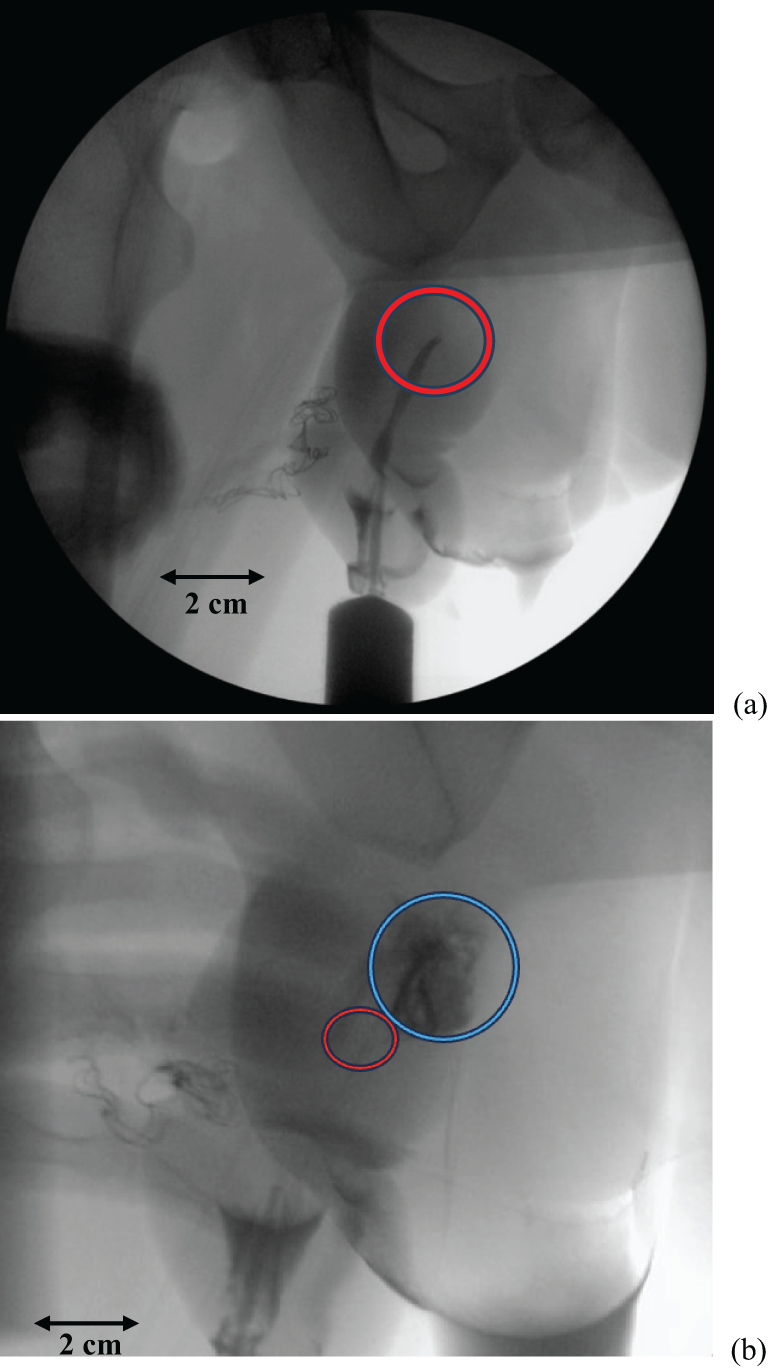

A preoperative retrograde urethrogram (RUG) was performed which demonstrated extravasation at the mid penile urethra (Figure 1a and b). Cystoscopic evaluation demonstrated a circumferential urethral avulsion at the level of the mid-penile urethra.

Figure 1: (a) Intra-operative retrograde urethrogram demonstrating an abrupt cutoff to contrast passage in the mid-penile urethra (red circle). (b) Intra-operative retrograde urethrogram demonstrating extravasation of contrast at the mid-penile urethra (blue circle) just proximal to the abrupt cutoff of contrast passage from Figure 1a (red circle)